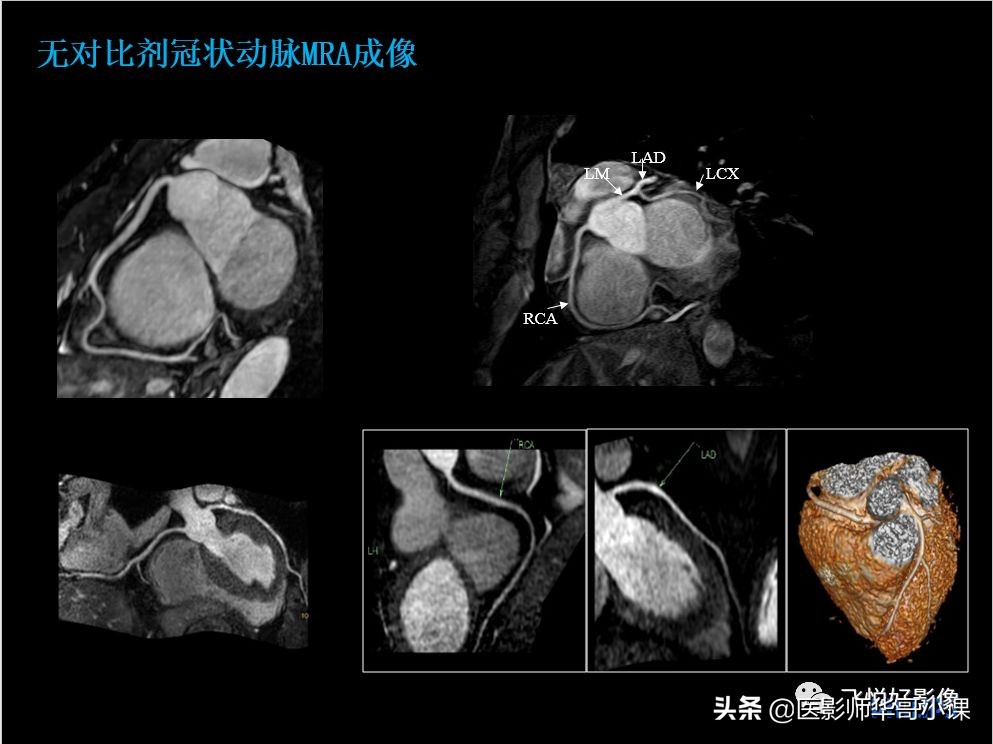

本期内容为无对比剂冠状动脉MRA、CMR心梗病例。飞利浦独特的极速冠状动脉MRA技术快至两分钟便可得到高质量的冠脉图像。